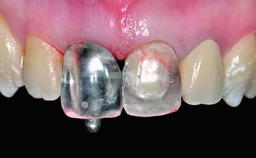

A 32-year-old female Caucasian patient with a compromised maxillary right central incisor was referred to us by a general dentist. Her chief complaints were discomfort and mobility of tooth 11 with unsatisfactory esthetics due to discoloration. The patient reported a previous trauma, some years earlier, as the origin of pathology on the afflicted tooth. Anamnesis was negative for any other dental or periodontal pathology in the remaining dentition. The patient did not take any medication and reported to be a light smoker (5–10 cigs/day). She had high esthetic expectations of her treatment. The extraoral examination revealed a high smile line with full exposure of her maxillary teeth and surrounding soft tissue in the area between the second premolars.

Prosthesis Type FDP

Loading Protocol Conventional or early

Retention Screw-retained Screw-retained

Provisional Implant-Supported Prosthesis Prosthodontic margin > 3 mm apical to mucosal margin Prosthodontic margin > 3 mm apical to mucosal margin

Interim Prosthesis during Healing Fixed Fixed